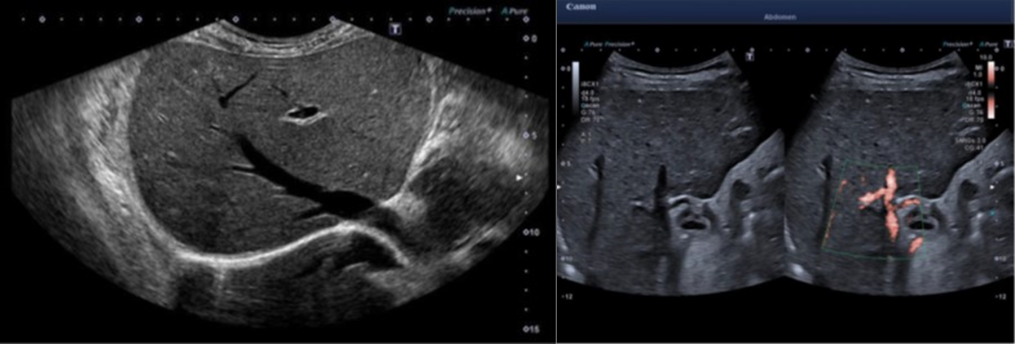

ÁÂ:¿ïÆ®¶ó ¿ÍÀÌµå ºä ¿ì:SMI 4¼¼´ë

¿©±â¿¡ Ç÷·ù·®ÀÇ ¹üÀ§¸¦ È®ÀåÇØ ´õ ³ôÀº ¼ÓµµÀÇ Ç÷·ùµµ °¡½ÃÈ­ÇÒ ¼ö ÀÖ°Ô µÆ°í, ³ëÀÌÁî ¿µ¿ª¿¡¼­ Clutter noise¸¦ ÁÙÀÓÀ¸·Î½á È£Èí Á¶ÀýÀÌ Èûµé¾ú´ø ȯÀÚ¿¡°Ô¼­µµ ÀûÀº ¾ÆÆ¼ÆÑÆ®·Î ¹Ì¼¼Ç÷·ù¸¦ º¸´Â °Ô °¡´ÉÇÏ´Ù.